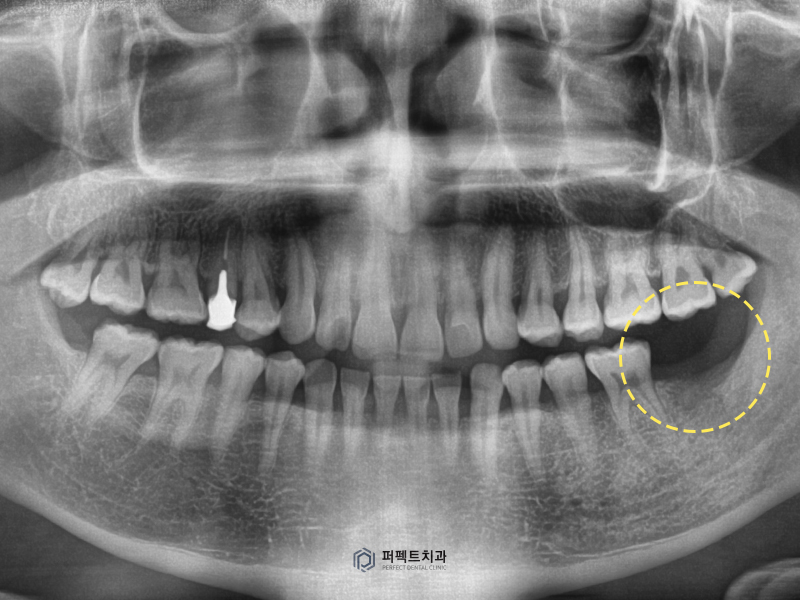

초진 사진을 보시면 왼쪽 아래 뒤 어금니 치아가 없는 것을 확인하실 수 있습니다. 빠진지는 5~6개월 정도 되신 상태이고, 임플란트 식립하는 수술을 시행하였습니다.

이 때 진단학적으로 중요한 부분은 치아가 만들어지기 전까지 배합되는 치아가 없다보면 위에 있는 치아가 아래로 쏟아지기 때문에 치아가 내려오지 않도록 고정하는 것이 중요합니다.